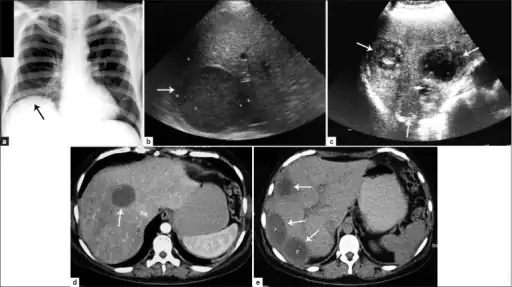

a) Amoebic liver abscess showing the elevation of the right hemi-diaphragm b)single large amoebic abscess and c) three amoebic hepatic abscesses. d) Contrasted computed tomography (CT) scan of a single abscess and e) three clear amoebic liver abscesses